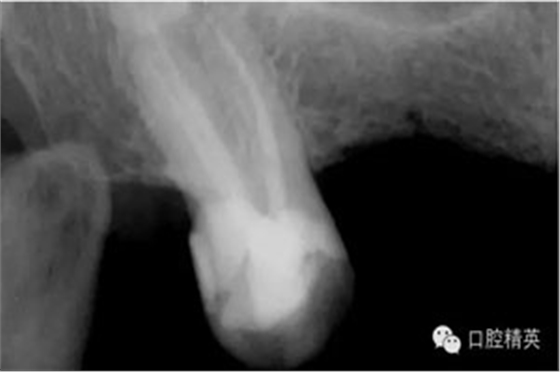

圖2患牙RCT后